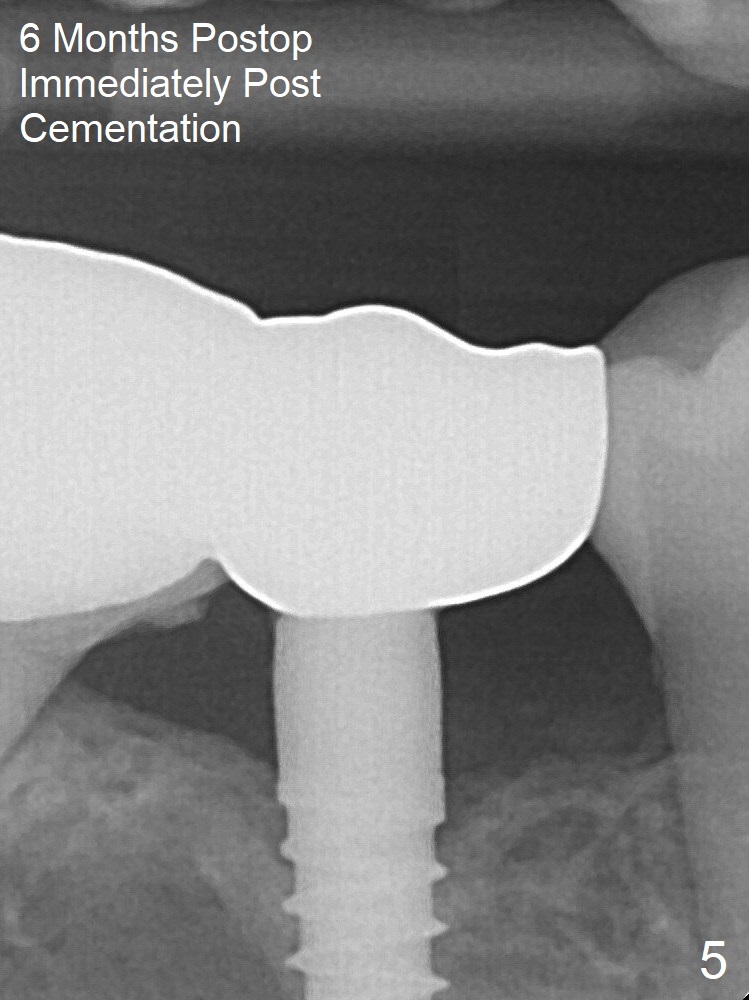

Impression is taken 5 months postop (Fig.4). Residual cement

mesial to the crown at #31 is later removed (Fig.5).